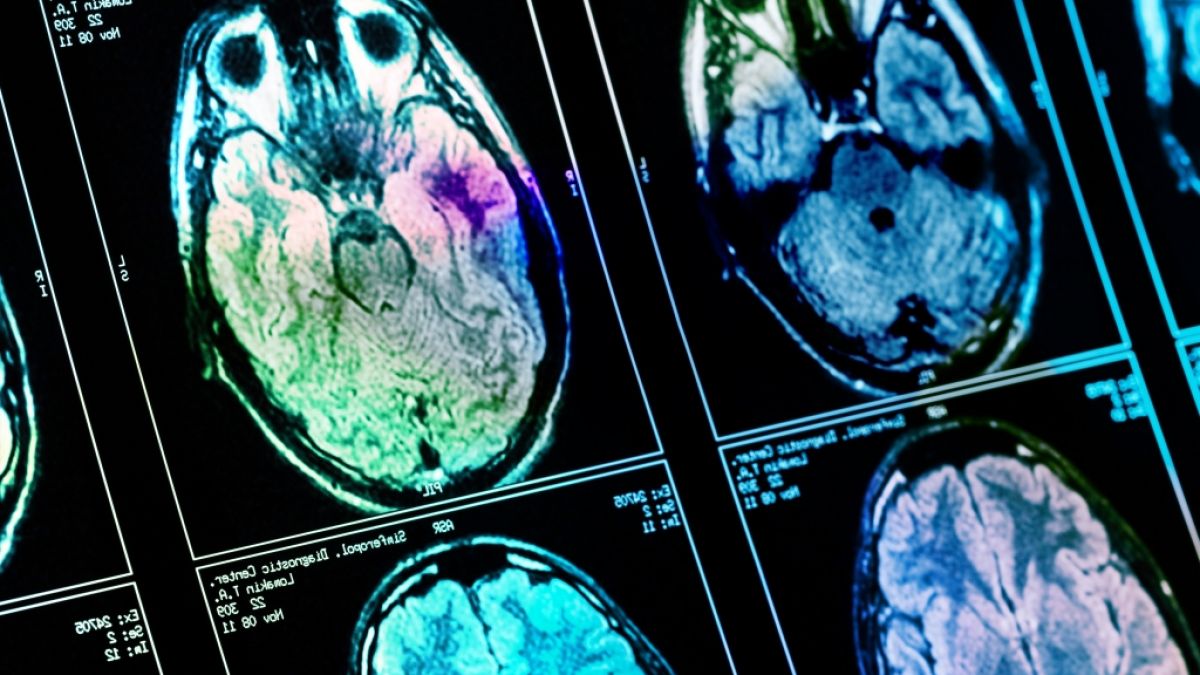

Was dumm macht: Diese fünf Gewohnheiten schränken die Gehirnleistung ein

Nicht nur Demenz kann die kognitive Leistung verschlechtern - auch ganz alltägliche Gewohnheiten können zu Denkproblemen führen. Welche Verhaltensweisen Sie unbedingt ändern sollten.

Noch immer wissen viele nicht, dass Alkohol nicht nur kurzfristig Einfluss auf das Gehirn und die Wahrnehmung hat. Wissenschaftler sind sich einig, dass bereits ein moderater aber regelmäßiger Konsum das Gehirn nachhaltig schädigt. Bei starken Trinkern stellte man in einer Untersuchung an fast 1.800 Verstorbenen fest, dass die Wahrscheinlichkeit für Gefäßschäden im Gehirn um 133 Prozent erhöht war.

Auch ehemalige Trinker hatten eine um 89 Prozent erhöhte Wahrscheinlichkeit als Menschen, die keinen Alkohol tranken. Zudem kommt es häufiger zu Schäden im Gehirn durch die sogenannten Tau-Fibrillen: Diese werden unter anderem mit Alzheimer in Verbindung gebracht und treten bei Trinkern 41 Prozent häufiger auf - ehemalige waren immer noch zu 31 Prozent häufiger betroffen.